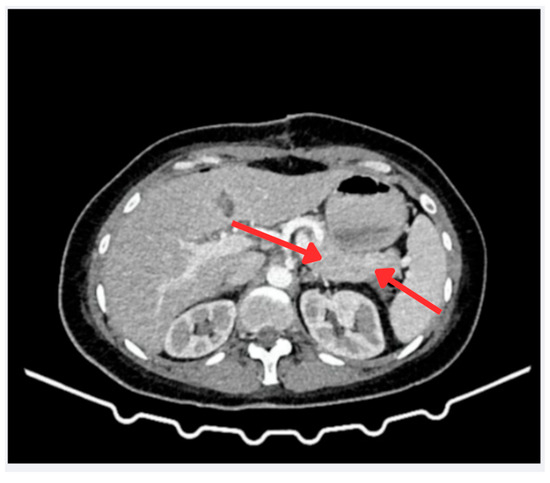

Postoperatively, the patient developed abdominal pain and peritoneal irritation. An abdominal CT scan revealed loculated fluid and gas bubbles near the surgical site, suggestive of a fistula. Following clinical deterioration and fever, a course of piperacillin–tazobactam (4.5 g every 6 h for 10 days) was initiated, and emergency laparotomy identified 1500 cc of hemoperitoneum. The blood cultures remained negative (see Figure 4). The histopathological findings, detailed in Table 2, confirmed the diagnosis of a neuroen-docrine tumor.

Figure 4.

Micrograph of a well-differentiated, grade 3 neuroendocrine tumor. Histological image at 400× magnification (field of view: 450 µm), showing nests of tumor cells separated by fibrous stroma. The red arrows indicate areas with round nuclei and granular chromatin, typical characteristics of this tumor type. The staining reveals a high cellular density, consistent with an elevated Ki-67 proliferation index.